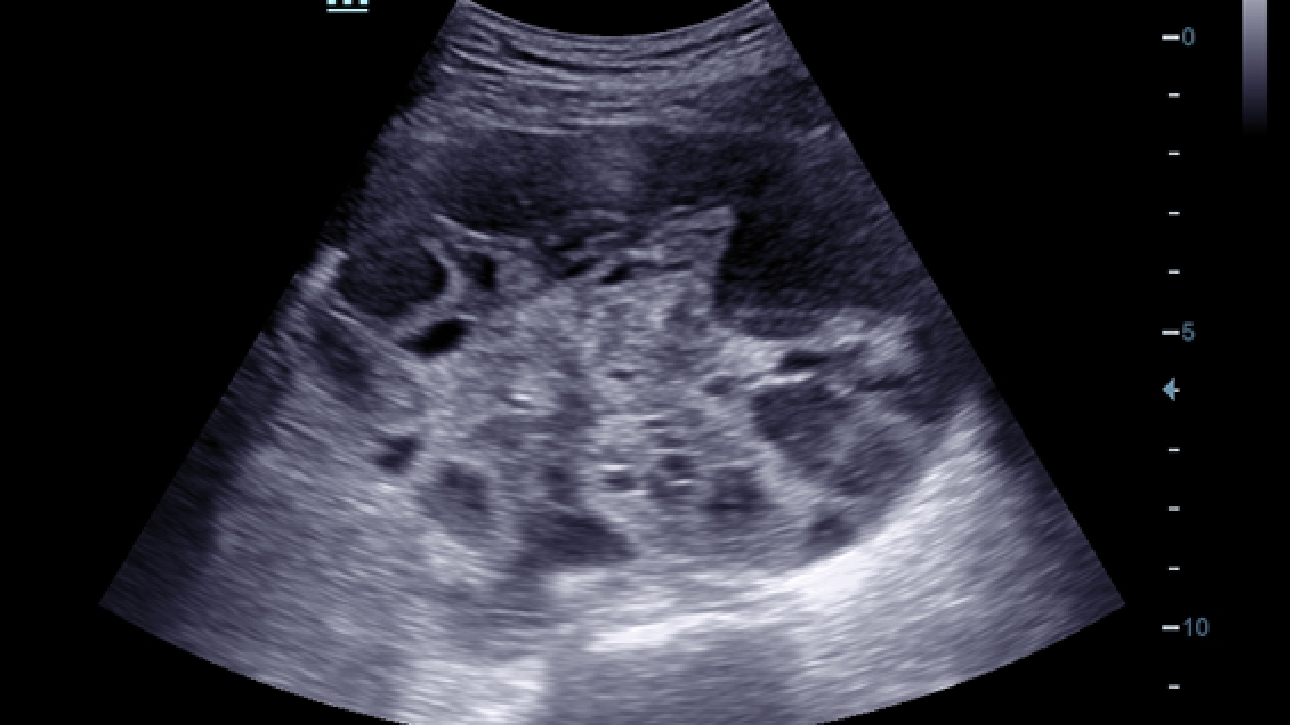

Klinische Bilder